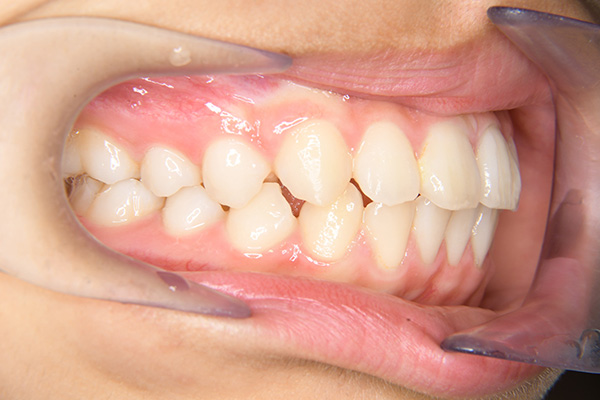

主訴 出っ歯 診断名 アングルⅡ級1類

初診時年齢 7歳0ヵ月 性別 動的治療期間 28ヵ月

口腔内所見 over jet 7.5mm,over bite 3.5mm,大臼歯関係はⅡ級 。Hellmanのdental ageはⅢAであり上突咬合を呈していた。

批評・予后 本来であれば永久歯歯列完成後に本格矯正治療を行って良い症例だが、患者さん(保護者)の強い希望から早期治療にて改善を行った症例である。バイオネーターを夜間就寝中に使用して咬合誘導を行った結果、前歯の前突感は解消され比較的緊密な咬合は得られたように思う。